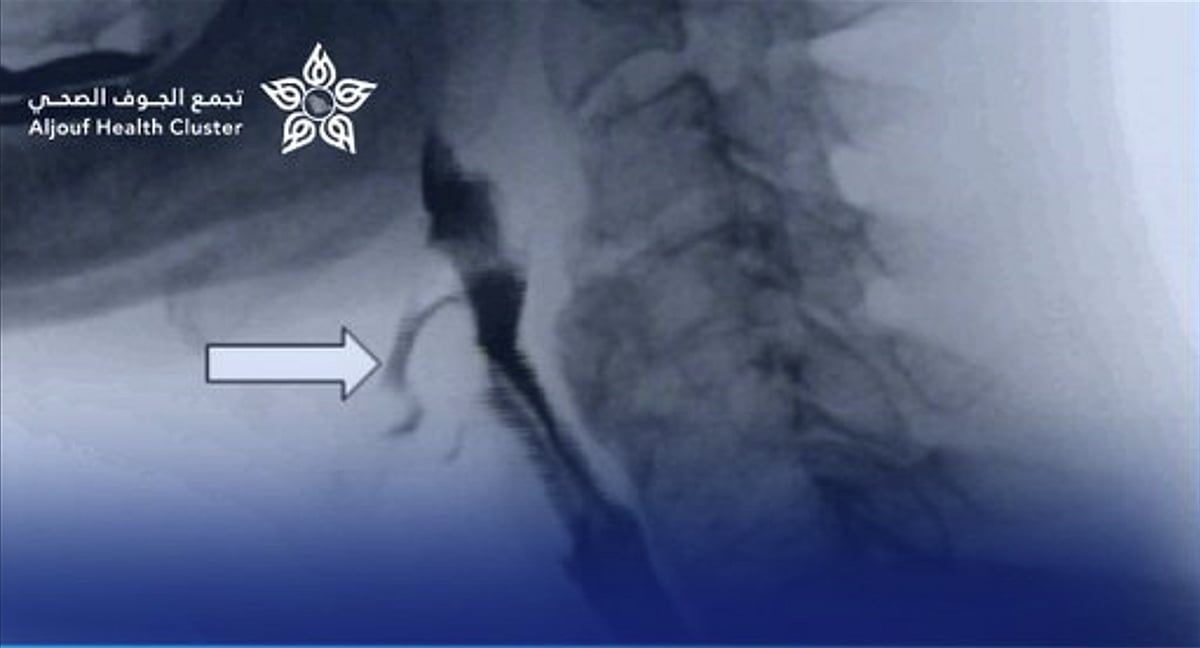

وأوضح التجمع الصحي بمنطقة الجوف أن الطفل كان يعاني من صعوبة شديدة في البلع واسترجاع متكرر للطعام، وتبيّن بعد الفحوصات وجود تضيق شديد في المريء يعيق مرور الطعام. وقد قام الفريق الطبي بإجراء عملية توسيع للتضيق باستخدام المنظار والموسعات الطبية المناسبة، تكللت بالنجاح الكامل دون أي مضاعفات.